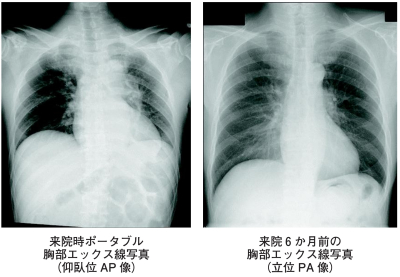

検査所見 : 心電図は、心拍数 108/分の洞調律で、肢誘導および胸部誘導ともに低電位で、Ⅱ、Ⅲ、aVf に ST 上昇を認めた。ポータブル撮影機による仰臥位の胸部エックス線写真及び6 か月前に撮影された立位の胸部エックス線写真を別に示す。胸部エックス線写真を見比べながら、研修医が指導医に所見や解釈を報告した。

適切なのはどれか。

a. 「6か月前と比較して胃泡が多くなっています」

b. 「本日の写真では下行大動脈が認められません」

c. 「本日の写真では著しい気管の偏位が認められます」

d. 「6か月前と心拡大の程度を比較するのは困難です」

e. 「いずれの写真でも CP アングル<肋骨横隔膜角>は鋭なので胸水貯留はありません」